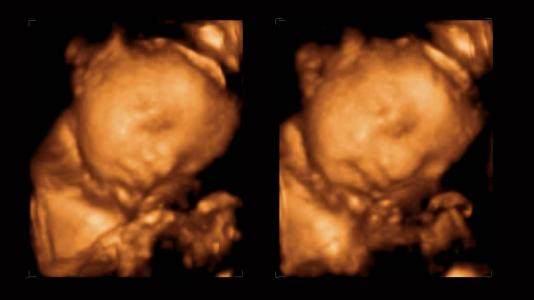

脐带绕颈就是脐带缠绕在宝宝脖子上,这是一种很常见的现象。大多数是绕颈一圈,少数绕颈两圈,三圈以上的很少见,主要的原因有脐带过长,羊水过多,胎儿体形较小,这样胎儿活动范围就大,在子宫里翻转,就会容易导致绕颈!多数情况下,脐带绕颈会自动解锁!

事实上,脐带绕颈这是分娩时常见的现象。如果是绕颈一周的情况下,对顺产没有影响的。两周的话一般问题也不大,当宝宝的头部娩出时,助产士会帮助宝宝把脐带绕出来。在孕晚期,脐带绕颈是正常的哦~